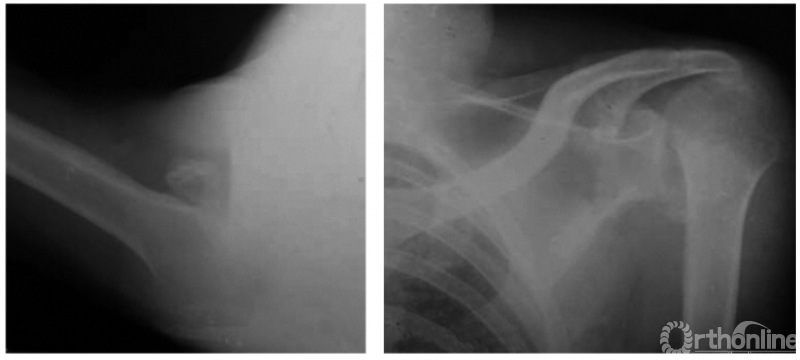

例3:肩关节喙突内下方脱位并大结节及肩峰端骨折(如下图)。

例4:肩关节盂下脱位并解剖颈骨折:致肱骨头仍滞留在盂下,而远折端回至关节盂部,形成假关节(如下图)。